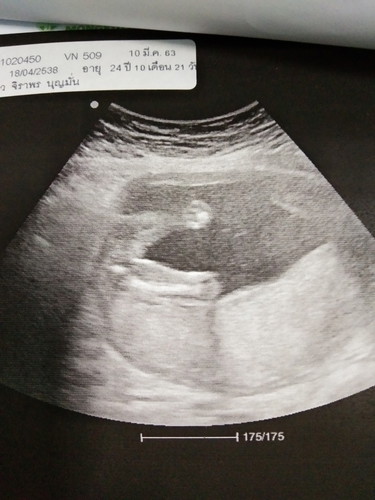

เสี่ยงมดลูกแตก

เมื่อวันที่ 10 เราได้ไปหาหมอมาค่ะ คุณหมอบอกว่าเราเสี่ยงที่จะมดลูกแตก และเสียชีวิตได้ทั้งแม่และลูก เราเครียดมากเลย คุณหมอก็ถามว่าทำไมปล่อยให้มีคนที่ 4 ทั้งๆที่เขาห้ามมีเกิน 2-3 คน เราก็พูดไม่ออก หน้าเสียเลย ตอนนี้เราท้องได้ 5 เดือนแล้ว ใครเคยมีปัญหาแบบนี้ หรือ ประสบการณ์ ช่วยมาแชร์ให้เราฟังหน่อย ตอนนี้เรากลัวมาก หมอ รพ.มงกุฎวัฒนะ เราว่าจะเปลี่ยน รพ. มาที่ รพ.ภูมิพล ช่วยแนะนำให้หน่อยค่ะ

แม่ท่านนี้น่าจะผ่าคลอดมาแล้ว3ครั้งค่ะและคนที่4กำลังตั้งท้องอยู่ในตอนนี้ แม่ๆบางท่านอาจจะ งงๆกับคำถาม ถ้ากรณีที่ผ่าคลอดจากที่ไปอบรมตั้งครรภ์มาน่ะค่ะ คุณหมอไม่แนะนำให้เกิน3ท้องค่ะ เพราะมีความเสี่ยงในการคลอดลูกและตัวแม่เอง ลองนึกภาพน่ะค่ะแผลที่ถูกกรีดที่เดิมๆซ้ำๆหลายๆรอบถ้าเปนแผลด้านนอกเรามองเห็นแต่นี่เปนแผลด้านในคงไม่ปลอดภัยแน่นอน มีความเสี่ยงที่จะมดลูกแตกได้ เพราะขนาดท้องแต่ละท้องก็ไม่เท่ากันเช่น ท้องที่1ท้องจะเล็กกว่าท้อว2-3-4จะยิ่งมีขนาดใหญ่ขึ้นและบาดแผลที่เคยผ่าซ้ำๆก็จะขยายขึ้นตามไปอีกค่ะ คุณหมอเรยกังวลกับความเสี่ยงตรงนี้เรยแนะนำคุณแม่ไปแบบตรงๆเรยให้ไปปรึกษา รพ.อื่นดูเผื่อจะมีคุณหมอท่านไหนที่รับมือได้กับเคสนี้ค่ะ ในเมื่อแม่ตั้งท้องมาได้ขนาดนี้แล้วก็ต้องทำใจเผื่อไว้ด้วยน่ะค่ะ ถ้าโชคดีก็คงไม่มีอันตราย แต่ถ้าโชคร้ายก็โทษใครไม่ได้ค่ะ **ทางที่ดีแม่ลองปรึกษาหลายๆ รพ.ดูน่ะค่ะ อาจจะไม่ได้เลวร้ายอย่างที่คิด **ยังไงก็ขอให้แม่และน้องคลอดง่ายปลอดภัยทั้งคู่น่ะค่ะ **แม่ๆบางท่านบอกว่าคลอดมาแล้ว5-8-12ไม่เห็นเปนอะไร ก็จริงค่ะ ถ้าคลอดธรรมชาติ จะคลอด 20-50-100คนก็ได้จร้าถ้าไหววว😁